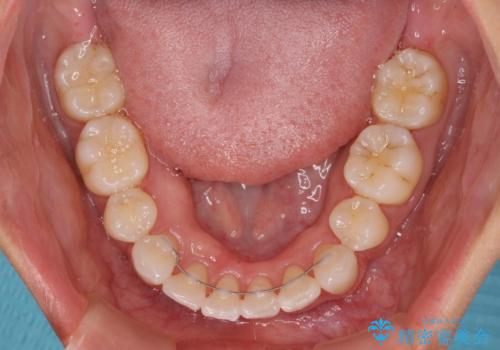

途中妊娠と出産がありましたが、予定よりも早く治療を終えることができました。